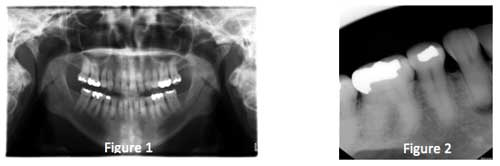

The case presented involves a mandibular canine that not only had a devitalized pulp, but also demonstrated a canal that had calcified for unknown reasons (Figs. 1 and 2). In addition to an asymptomatic periapical lesion, the patient presented with an extraoral fistula.

Several attempts at negotiating the canal were unsuccessful (Figs. 3 and 4), but after each visit, a thick mix of calcium hydroxide was densely packed into the preparation (Fig. 5). After approximately nine months, the lesion was seen to have resolved solely through the chemical reduction in the “bio load” present in the root canal system. The artificially created canal was then sealed with glass ionomer, followed by composite (Fig. 6). Of note, there is no sealer and no gutta percha anywhere in this tooth! One-year radiographic follow-up shows complete healing of the apical lesion (Fig. 7).